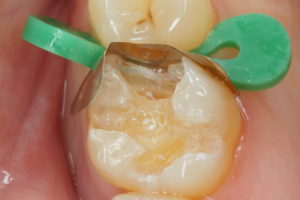

4枚目は、隣の歯にプラスティックがくっつかないよう、隔壁をしているところです。この隔壁にはいろいろなやり方があり、これはその1例です。虫歯の大きさによって、隔壁を作る器具も異なります。